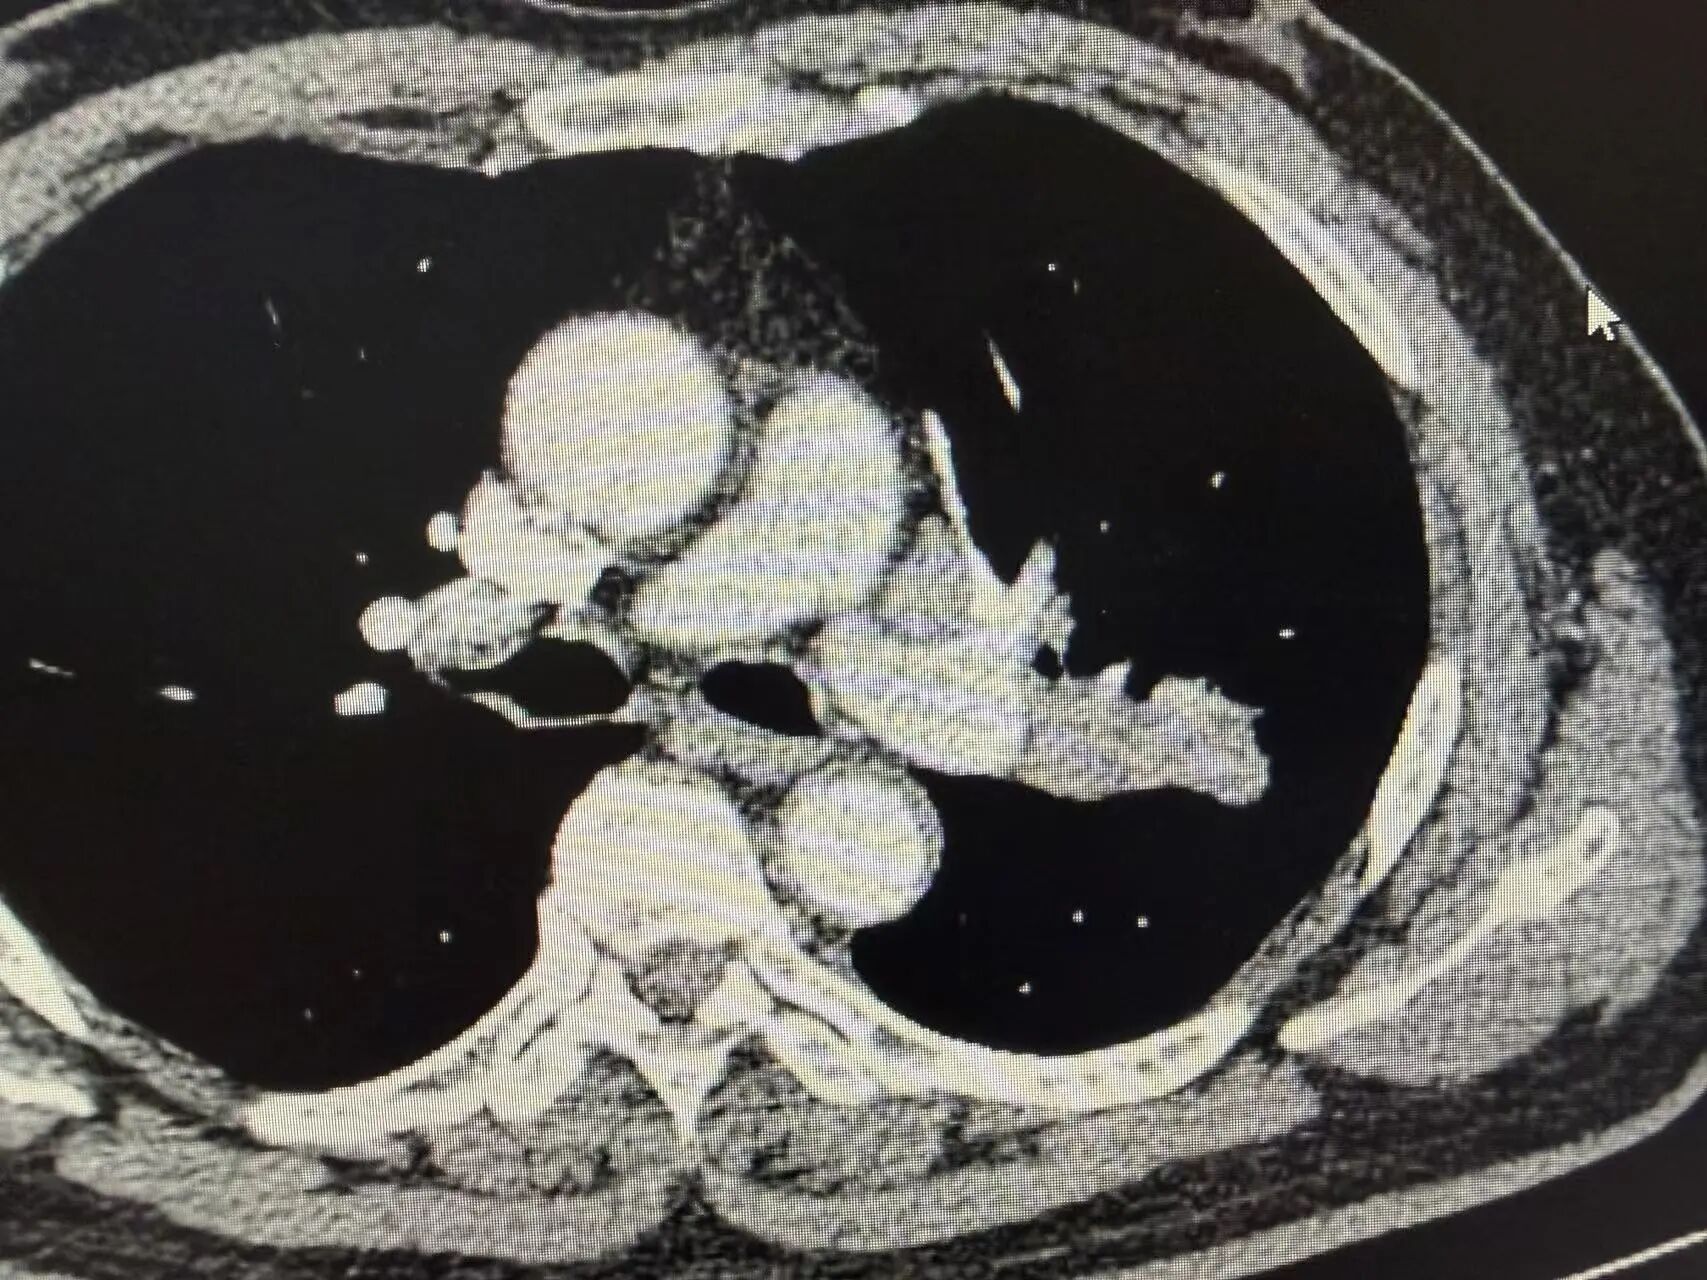

胸部增强CT结果显示:左上肺可见明显占位性病变,体积较大,同侧肺门淋巴结伴随肿大。后续穿刺病理活检明确诊断为肺鳞状细胞癌,结合淋巴结转移情况,分期为局部晚期(Ⅲa期)。

新辅助治疗前CT影像